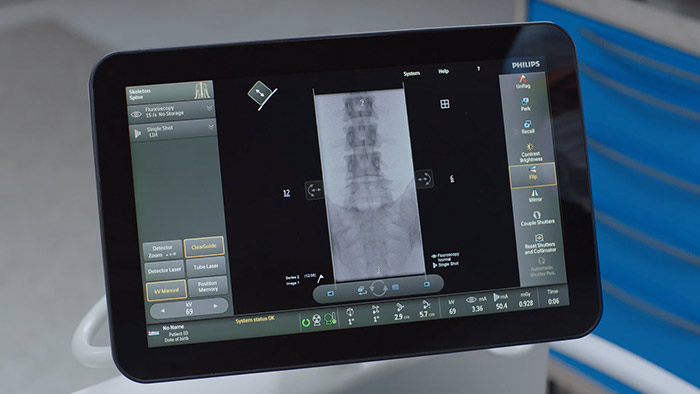

Módulo de pantalla táctil (TSM)*

Como una adición a la plataforma Zenition 70, el módulo de pantalla táctil (TSM) admite el control desde la mesa para los cirujanos durante los procedimientos. A través de la pantalla táctil, puede seleccionar, arrastrar y hacer zoom de los elementos con facilidad. Esto significa que puede ver imágenes al instante, lo que le brinda un mayor control de la imagen durante los procedimientos. *El TSM está disponible como opción solo en Zenition 70